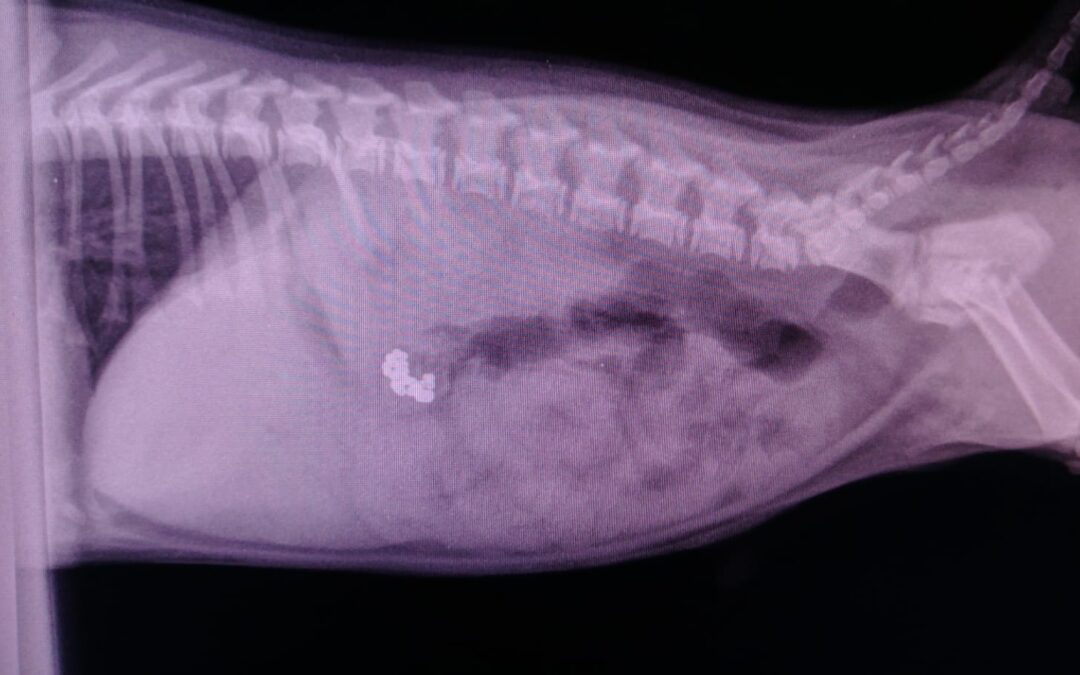

Rugus XR